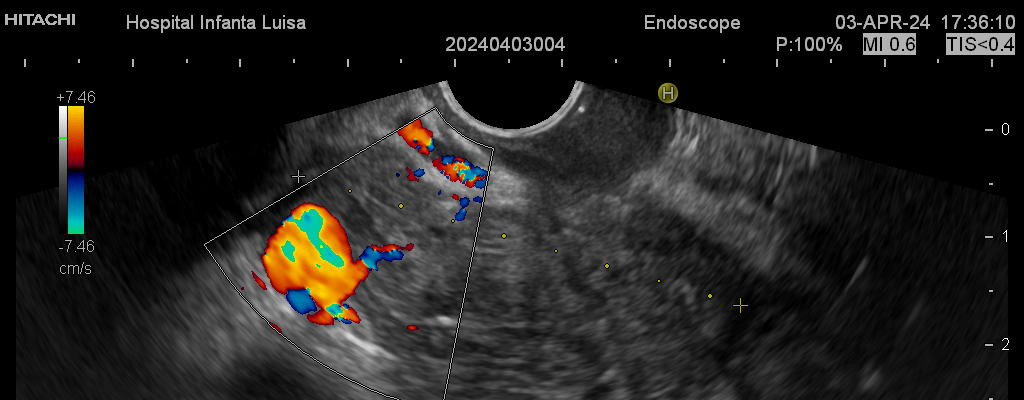

Ecoendoscopia

La Ecoendoscopia o Ultrasonografía endoscópica (USE) consiste en la exploración del tracto digestivo superior (principalmente), o de los últimos centímetros del tracto digestivo inferior (recto, generalmente), con un tipo de endoscopio especial que se llama ecoendoscopio.

La Ecoendoscopia, como su nombre indica, combina dos tipos de técnicas: la endoscopia y la ecografía, pues nos aporta simultá…